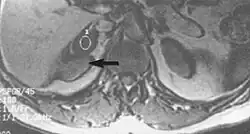

Flow can manifest as either an altered intravascular signal (flow enhancement or flow-related signal loss), or as flow-related artifacts (ghost images or spatial misregistration). Flow enhancement, also known as inflow effect, is caused by fully magnetised protons entering the imaged slice while the stationary protons have not fully regained their magnetization.[1] The fully magnetized protons yield a high signal in comparison with the rest of the surroundings. High velocity flow causes the protons entering the image to be removed from it by the time the 180-degree pulse is administered. The effect is that these protons do not contribute to the echo and are registered as a signal void or flow-related signal loss (Fig. 2).[1] Spatial misregistration manifests as displacement of an intravascular signal owing to position encoding of a voxel in the phase direction preceding frequency encoding by time TE/2.The intensity of the artifact is dependent on the signal intensity from the vessel, and is less apparent with increased TE.[1]